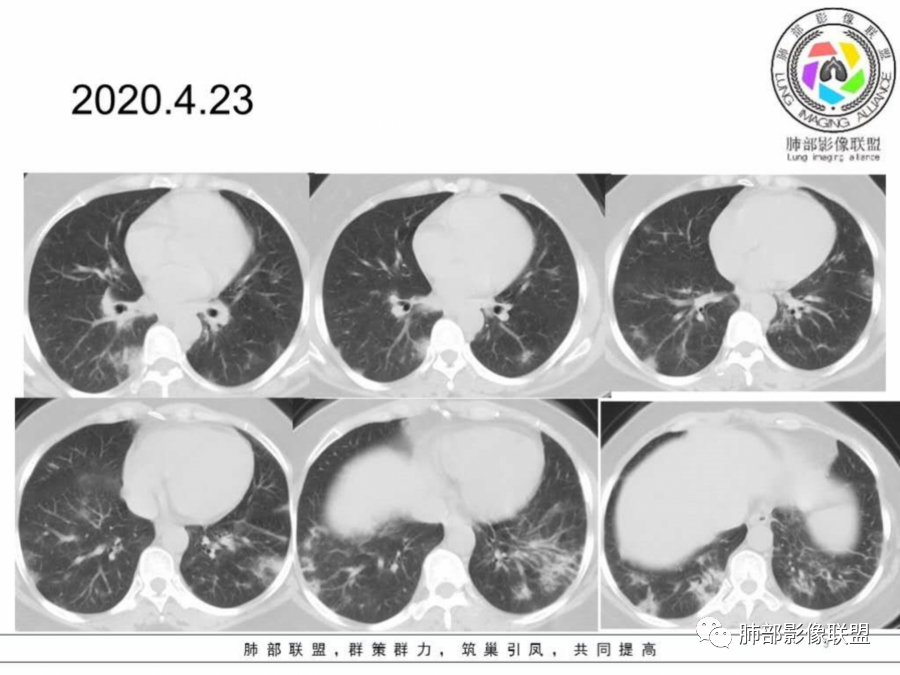

胸CT:4月23:双下肺渗出影,以外周胸膜下为主,4月29日病灶增多,部分沿支气管血管束分布,渗出影病灶密度较前增高。

胸CT:4月23日:支气管血管束及胸膜下分布实变及磨玻璃影,4月29日病灶增多。

两肺胸膜下外周为主多发磨玻璃影、实变影,非叶段分布,间质受累,抗感染治疗效果不佳。

4月23日两肺叶位于胸膜下分布多发散在斑片状磨砂影,内见细网格征,4月29复查对比,大部份病灶收收,范围减少,且边缘平直,内收;考虑病毒肺炎!

这个病变其实也就是周围间质的病变,有细网格征及碎石路征,这是典型的OP样改变,外围胸膜下,下肺明显,有一定的此起彼伏,影像只能判断到OP。